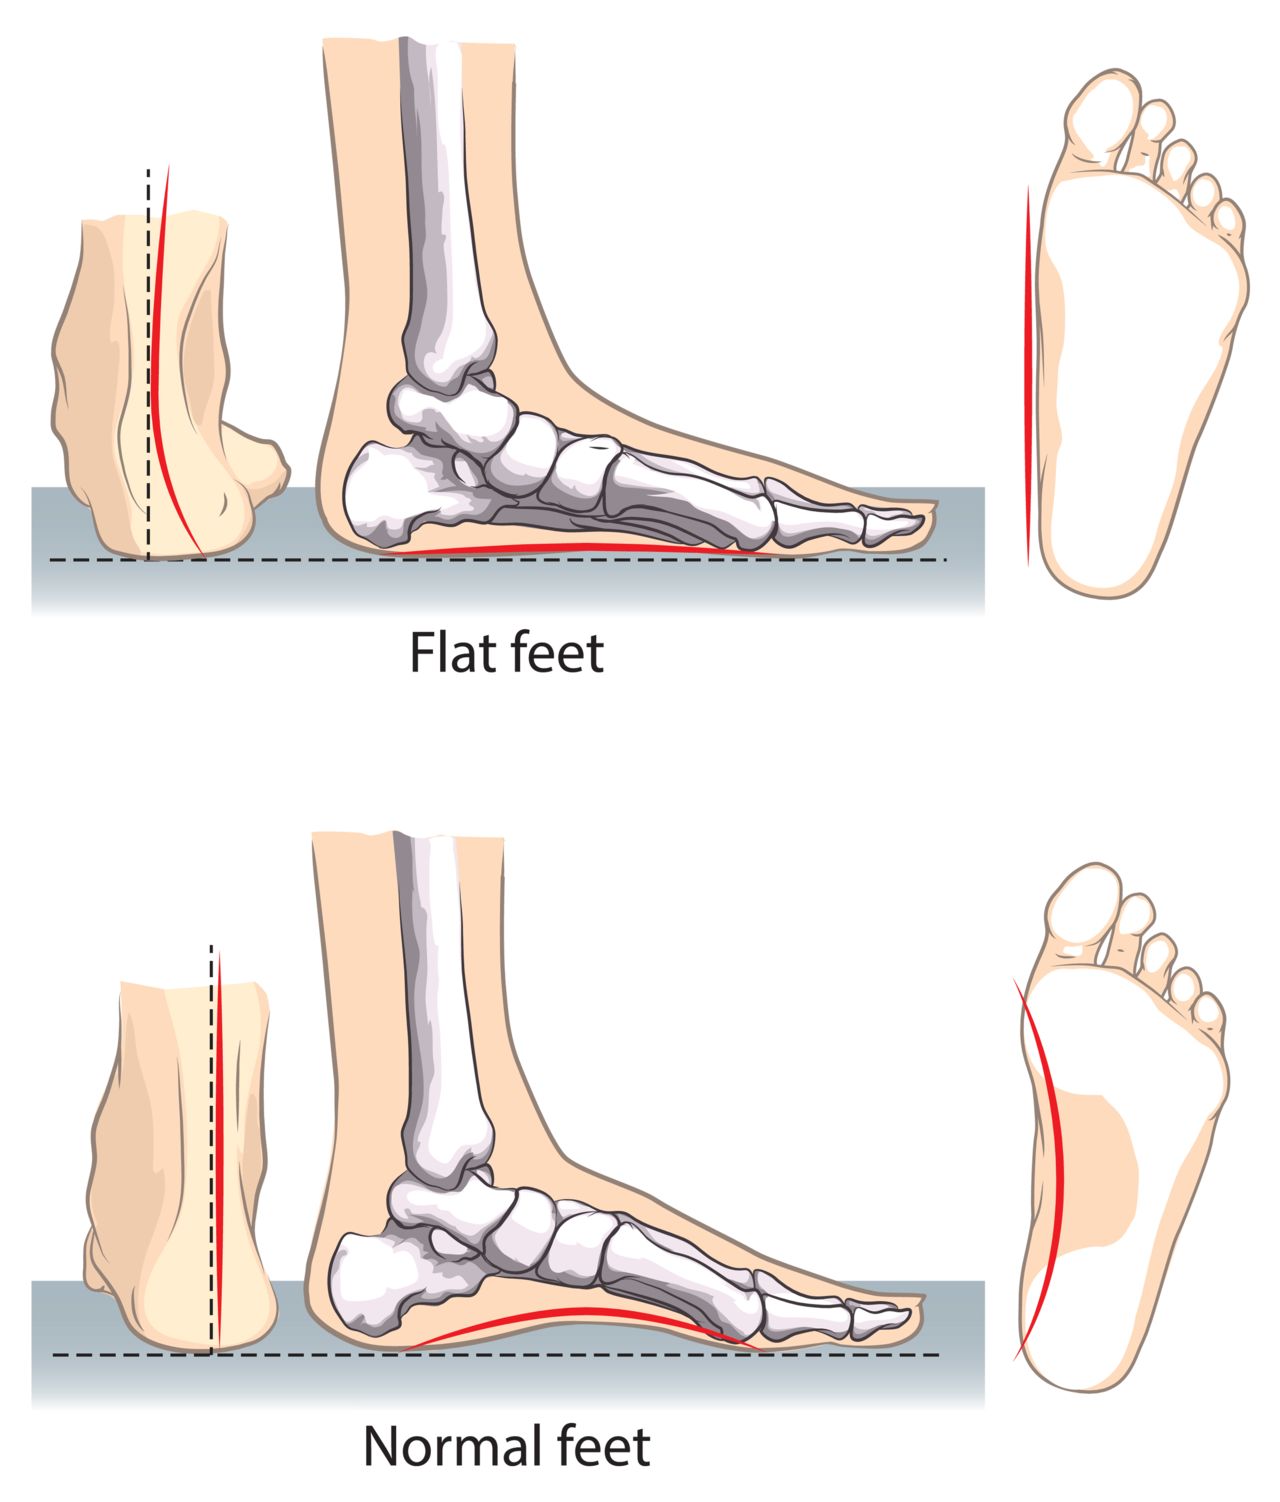

pictures of flat feet

Foot Postures: What It Means for Your Feet?

FLAT FOOT- Definition, Symptoms, Causes & Rehabilitation Exercises

The term “flat foot” is a generic and mis-leading description given for …

Flat Feet and High Arched Feet | Things to Know – Custom Rehab

Flat Foot: Symptoms, Causes And Treatment Of Pes Planus